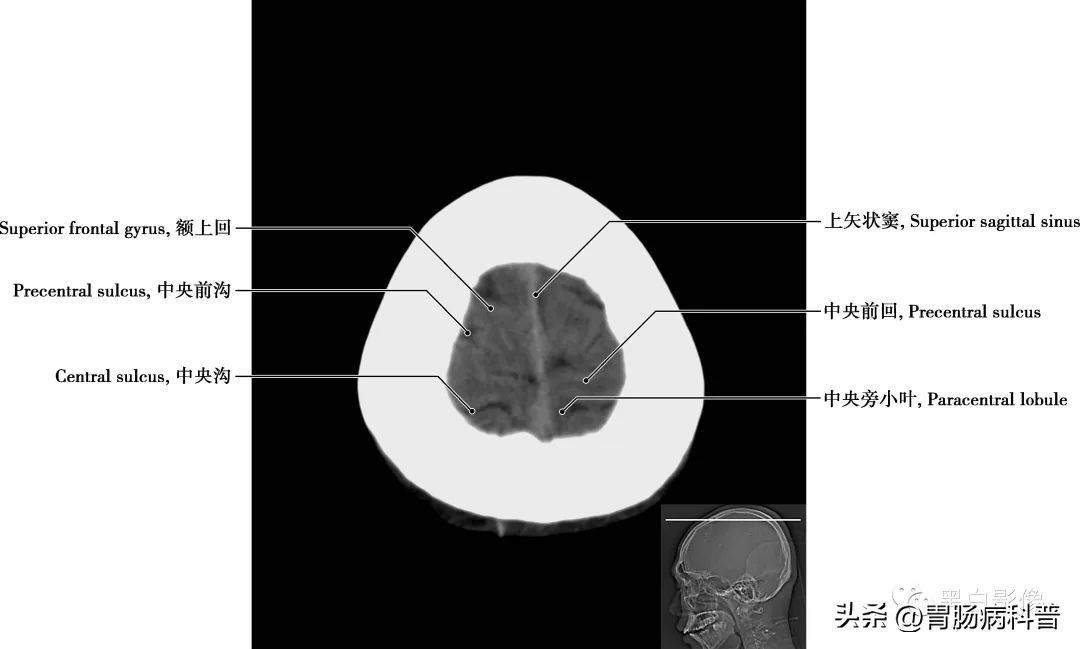

图1-1-2 经上矢状窦轴位切面

上矢状窦 为单一的硬脑膜静脉窦,位于大脑镰上缘,前起于盲孔,后连于窦汇;收纳大脑上静脉、硬脑膜静脉和颅骨静脉的血液,注入窦汇或直接分流至左、右横窦;通过顶、枕部导血管与颅外静脉交通。此外,脑脊液经蛛网膜颗粒最后入矢状窦